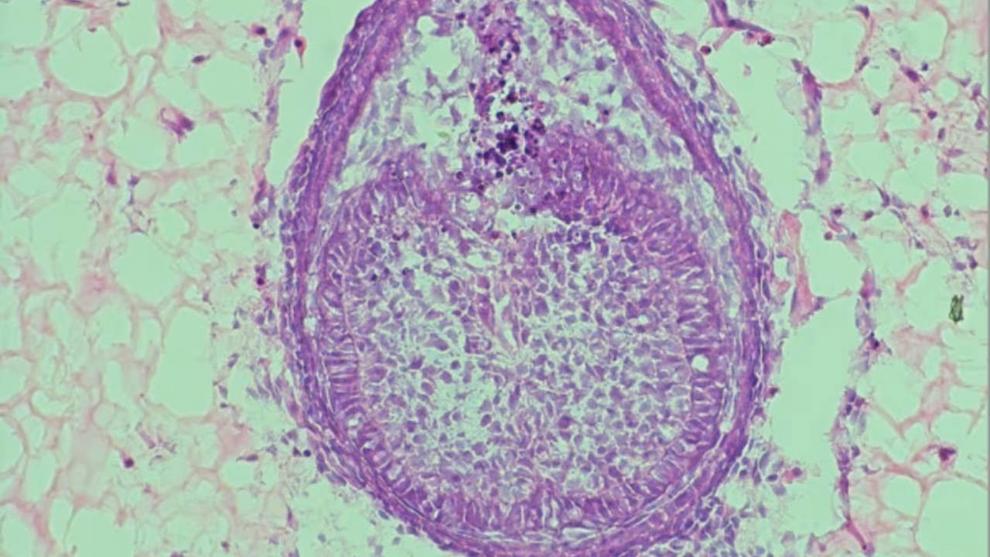

دکتر آنا آنجلوا ولپونی (Ana Angelova Volponi) از کینگز کالج لندن، نزدیک به بیست سال است که روی رشد دندانها در محیط آزمایشگاهی کار میکند. او در سال ۲۰۱۳ عضوی از تیمی بود که موفق شد از ترکیب سلولهای انسان و موش، دندانی واقعی رشد دهد.

به گفته ولپونی، ایده رشد دندان در محیط مصنوعی به دهه ۱۹۸۰ برمیگردد. در پژوهش سال ۲۰۱۳، او و تیمش نخستین بار سلولهای لثه بزرگسال انسان را با سلولهای پیشساز دندان از جنین موش ترکیب کردند تا جوانهای از دندان بسازند.

این محیط رشد که با عنوان «اسکفلد» (Scaffold) شناخته میشود، در شکلگیری دندان نقشی حیاتی دارد. تمرکز پژوهش اخیر ولپونی نیز بر توسعه همین ساختار بوده است. در حالیکه نسخه ۲۰۱۳ از کلاژن ساخته شده بود، نسخه جدید از هیدروژل استفاده میکند؛ مادهای پلیمری با درصد بالای آب که محیطی طبیعیتر برای رشد سلولها فراهم میآورد.

Xuechen Zhang، دانشجوی دکترا و همکار این پروژه، فرایند را اینگونه توضیح میدهد:

«سلولهای جنین موش را جمعآوری میکنیم، با هم ترکیب مینماییم و تودهای کوچک از سلولها (Pellet) میسازیم. سپس آن را داخل هیدروژل تزریق کرده و حدود هشت روز رشد میدهیم.»